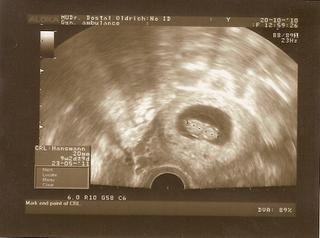

Ahoj holky, tak jsem byla dnes po dlouhém měsíci v poradně a vše je v pořádku . Květošek měří 6 cm a má se čile k světu. Výsledky z krve- genetika jsou negativní, takže ještě aby byl za 6 dní u Poláka ultrazvuk v pořádku a budeme spokojení. Do poradny teď budu chodit každých 14 dní, tak snad se nic nesemele a miminko donosím. Mám klidový režim, takže pro jistotu polehávat.

Ahoj holky, dnes jsme byli na tom screeningu u Poláka. Mimi je zdravé, měří 7,58cm a odpovídá přesně dni IUI, tedy jsme 13+5tt. Pohlaví bohužel nevíme protože mimi bylo pořád otočené zády k nám. Fotka se vůbec nepovedla, trochu mě to i mrzí

@lenajsek Ahoj Leni, no ať se Polák snažil jak chtěl, tak mimčo si to co má mezi nožičkami úzkostlivě hlídalo a tajilo. Některé holky už to vědí ve 12tt. Tak třeba 10.1 na velkém ultrazvuku se nám mimi ukáže 😉 . Opožděně gratuluji Lukáškovi k jeho významnému jubileu 🙂 a přeji mu hodně zdravíčka, štěstíčka, hodné rodiče a neustálý úsměv na rtech 😉.